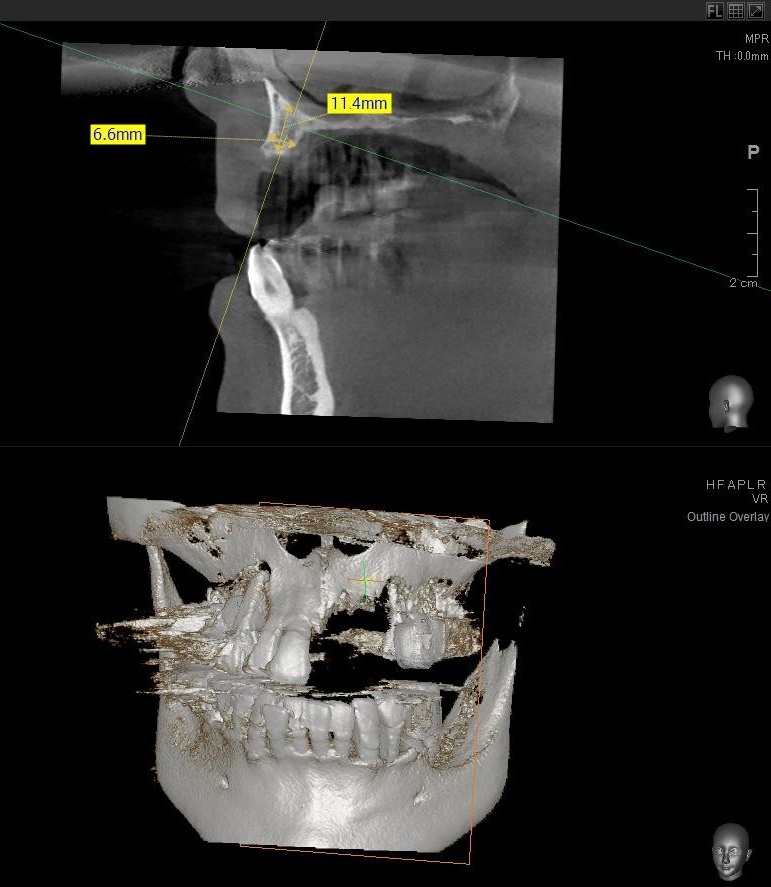

今回の患者様はインプラント植立を希望され、左上1番目・2番目・3番目の3本の植立が決まりました。

ドリルの先端を細い物から徐々に大きい物に変えながら、植立するインプラント体のネジの部分を除いた胴の部分の太さに合わせた大きさの穴を開けていきます。

開けた穴に、専用道具を使ってネジを締めるように長さ2センチ程のインプラントを骨に埋め込んでいきます。

しっかりとインプラント埋め込まれた後は、動揺がないか、噛んだ時に当たらないかなどを確認して、最後にパノラマ写真を撮影して今回のオペは終了となりました。